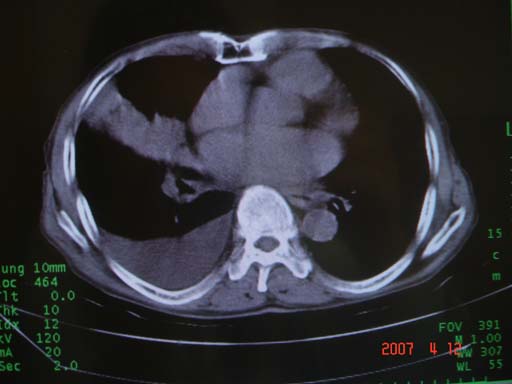

帮我 看看。男77岁咳嗽咯血2月发热2周!病人一般情况可 口痰为鲜红,有点象洗肉水(我看见他吐的痰了)

为何只有这么几幅图像?连纵隔窗都没有。但我发现上叶支气管显示不清,再加上年纪大,咯血等症状,恶性肿瘤首先得考虑。

考虑右肺新生物伴右中上肺阻塞性肺炎及含气不良,右侧胸腔积液。建议痰与纤支镜检查

考虑右侧中央型肺癌伴中上肺阻塞性肺炎、不张,胸腔积液。,建议支纤镜检查。

病灶局限在右肺中上叶,呈大片状实变影,内见空气支气管征,支气管分支较柔软,纵隔内未见肿大淋巴结.支持:感染性病变_1 大叶性肺炎.2 干酪性肺炎.

优先考虑右上肺干酪性肺炎并同侧中叶播散、胸腔积液。分析:右膈肌未见升高、纵隔未见明显右移,胸部各组淋巴结未见可疑肿大,中叶可见支气管铸形,肺野、肺门未见可确定肿块。

单从影像学上来看,该病人应首先考虑,右上肺感染(干酪性肺炎可能大)伴有右侧胸腔积液,理由如下:

1.病灶整体成宽基底征,而未见块状影

2.病灶内的透光区并不是含气支气管征,而像是坏死的肺组织后形成的

3.无肺不张的表现

4.纵隔那未见明显肿大淋巴结

右肺上叶实变,实变范围如此之大,如果用肺癌解释的化,应该是比较大的支气管开口发生完全阻塞,但观察上叶前后段支气管还是比较通畅,所以应考虑感染性病变,大叶性肺炎可能,建议抗炎治疗后复查。